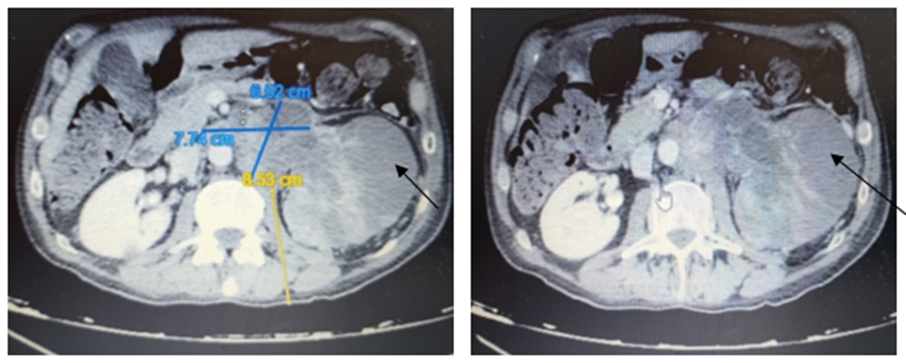

The patient was admitted under Urology care, and CT scan of thorax, abdomen and pelvis (Figure.2) was carried out.

Findings:

Thorax:

Correctly inspired pulmonary parenchyma, with mild emphysematous changes. Solid pulmonary nodule measuring 5 mm in size in the Right Lower Lobe (RLL). Left pleural effusion measuring 2 cm with associated compressive atelectasis. No mediastinal, hilar, or axillary adenopathy was observed.

Abdomen and pelvis:

Diffuse hepatic steatosis, with a 2.5 cm hypervascular lesion in segment IVA and another measuring 11 mm in segment III. Pancreas, right adrenal gland, and RK are unremarkable. Extensive hypodense mass occupying the LK and the proximal portion of the ureter, with signs of invasion of the ipsilateral RV. Left paraaortic mass left measuring 7,7 x 6,5 cm that could correspond with extension of tumour mass versus adenopathic conglomerate. Nodules in left perirenal area with size up to 22 mm suggestive of tumorous implants. Left suprarenal thickening with a nodule measuring 17 mm suggestive of secondary affection. Bladder and prostate without significant alterations. No suspicious characteristic bone lesions. Upper left urothelial neoplasm, locally advanced with signs of left RV invasion, and an extensive left paraaortic adenopathic conglomerate. Left suprarenal thickening with a nodule suggesting metastasis. Focal hypervascular, nonspecific hepatic lesions, to be evaluated by MRI. Solid pulmonary nodule measuring 5 mm in size in the RLL, to be evaluated on follow-ups. Left pleural effusion.

Figure 2: Enlarged LK with areas of hypocaptation of the renal parenchyma, suggestive of areas of necrosis (black arrows).Extensive hypodense mass occupying the LK and the proximal portion of the ureter, with signs of invasion of the ipsilateral RV (yelow arrow). Left paraaortic mass left measuring 7,7 x 6,5 cm (blue arrow). Nodules in left perirenal area suggestive of tumorous implants (white arrow).